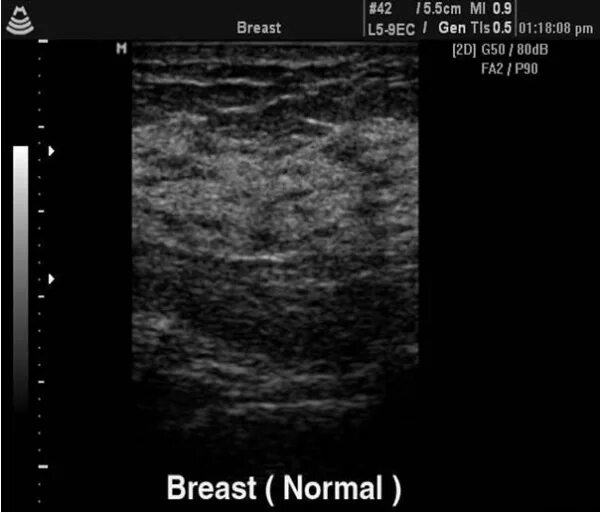

Когда делать узи молочных